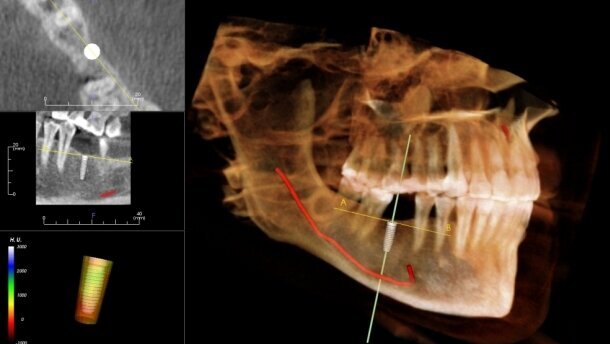

Oprogramowanie InVivo to nie tylko pomiary przedimplantacyjne. Oprogramowanie zawiera bogatą bazę implantów, które można wykorzystać do planowania położenia poszczególnych wszczepów. Planowanie odbywa się w obrębie trójwymiarowej rekonstrukcji tkanek pacjenta pod kontrolą poszczególnych rzutów 2D. Trajektorię tych ostatnich można łatwo modyfikować, dzięki czemu ocenimy położenie implantu w obrębie grubości wyrostka, a także uchwycimy relację jego ustawienia względem zębów sąsiednich i przeciwstawnych. W przypadku planowania pracy opartej na kilku implantach w obrębie szczęki lub żuchwy, czy chociażby chęci wykorzystania belki, możliwe jest automatyczne ustawianie równoległości długich osi poszczególnych wszczepów.

W przypadkach wymagających większej precyzji, gdzie odległość od ważnych struktur anatomicznych jest niewielka, z pomocą przyjdą narzędzia do ich oznaczania. Wyznaczanie przebiegu kanału nerwu zębodołowego dolnego czy dna zatoki szczękowej nie stanowi żadnego problemu. Wszystko dzieje się intuicyjnie, krok po kroku. Po oznaczeniu wymienionych struktur, system sam pilnuje ich odległości od implantu ostrzegając, gdy dystans ten staje się niebezpiecznie mały.